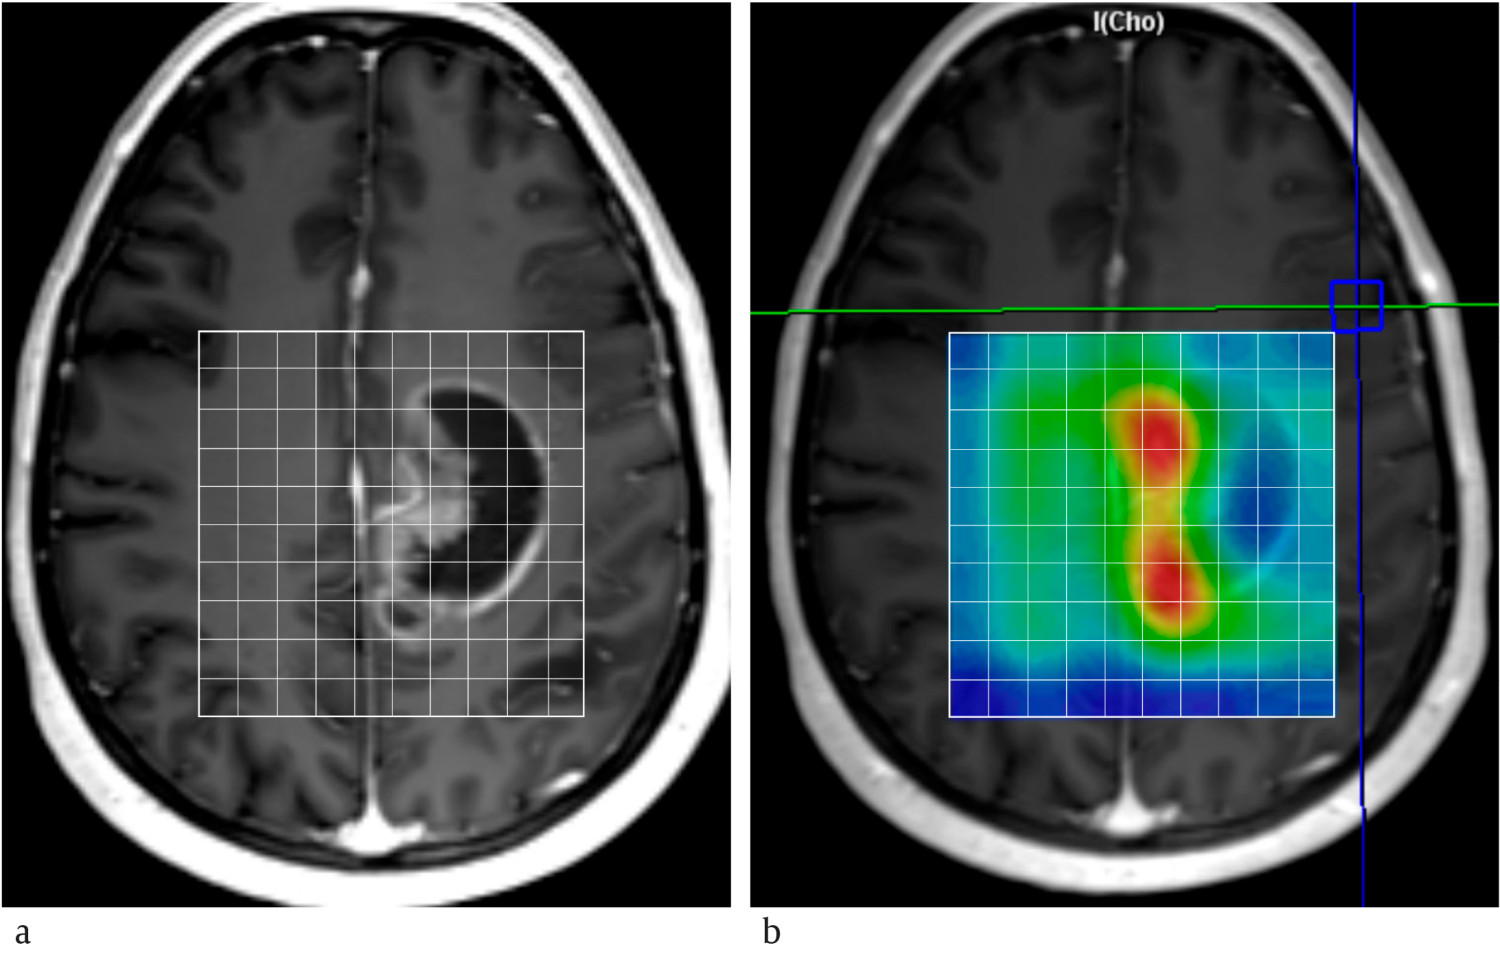

Hvert år diagnostiseres omtrent 300 pasienter i Norge med malign primær hjernesvulst, hvorav rundt 250 er høygradige gliomer (8). MR-spektroskopi kan bidra til å skille mellom hjernesvulst og andre typer lesjoner som abscess og subakutt infarkt (9). Generelt har hjernesvulster forhøyet mengde kolin, laktat og mobile lipider samt redusert mengde N-acetylaspartat og kreatin sammenlignet med tilsvarende normalt vev. Kolinmengden øker med malignitetsgraden, og forholdet mellom kolin og kreatin, og mellom kolin og N-acetylaspartat, er signifikant høyere i høygradige enn i lavgradige gliomer (figur 2) (10). Laktat og mobile lipider kan påvises i glioblastomer, men er også vanlig i metastaser.

Vi opplever at forventningene til MR-spektroskopi i klinisk praksis igjen er stigende. Dette skjer av to årsaker. Den ene er økt utbredelse av MR-skannere med høy feltstyrke (3 og 7 tesla). Høyere feltstyrke muliggjør deteksjon av metabolitter med lav konsentrasjon og differensiering av topper som overlapper ved lavere feltstyrke. Kjemisk skift-avbildning kan være en aktuell teknikk for å få til dette (figur 3). Metoden utføres over flere volumer, typisk 1 cm3, dekker et helt snitt eller volum av hjernen, og inneholder informasjon om regionale variasjoner i metabolittmengder. Ved St. Olavs hospital brukes denne teknikken ved omtrent halvparten av MR-spektroskopiundersøkelsene av hjernesvulster.